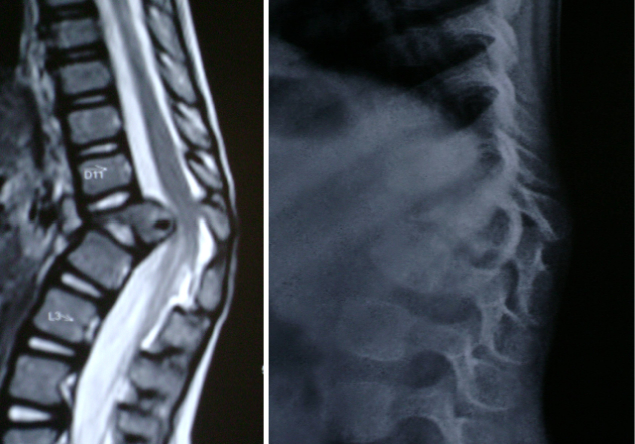

Preoperative MRI and x rays showing 65 degrees kyphosis